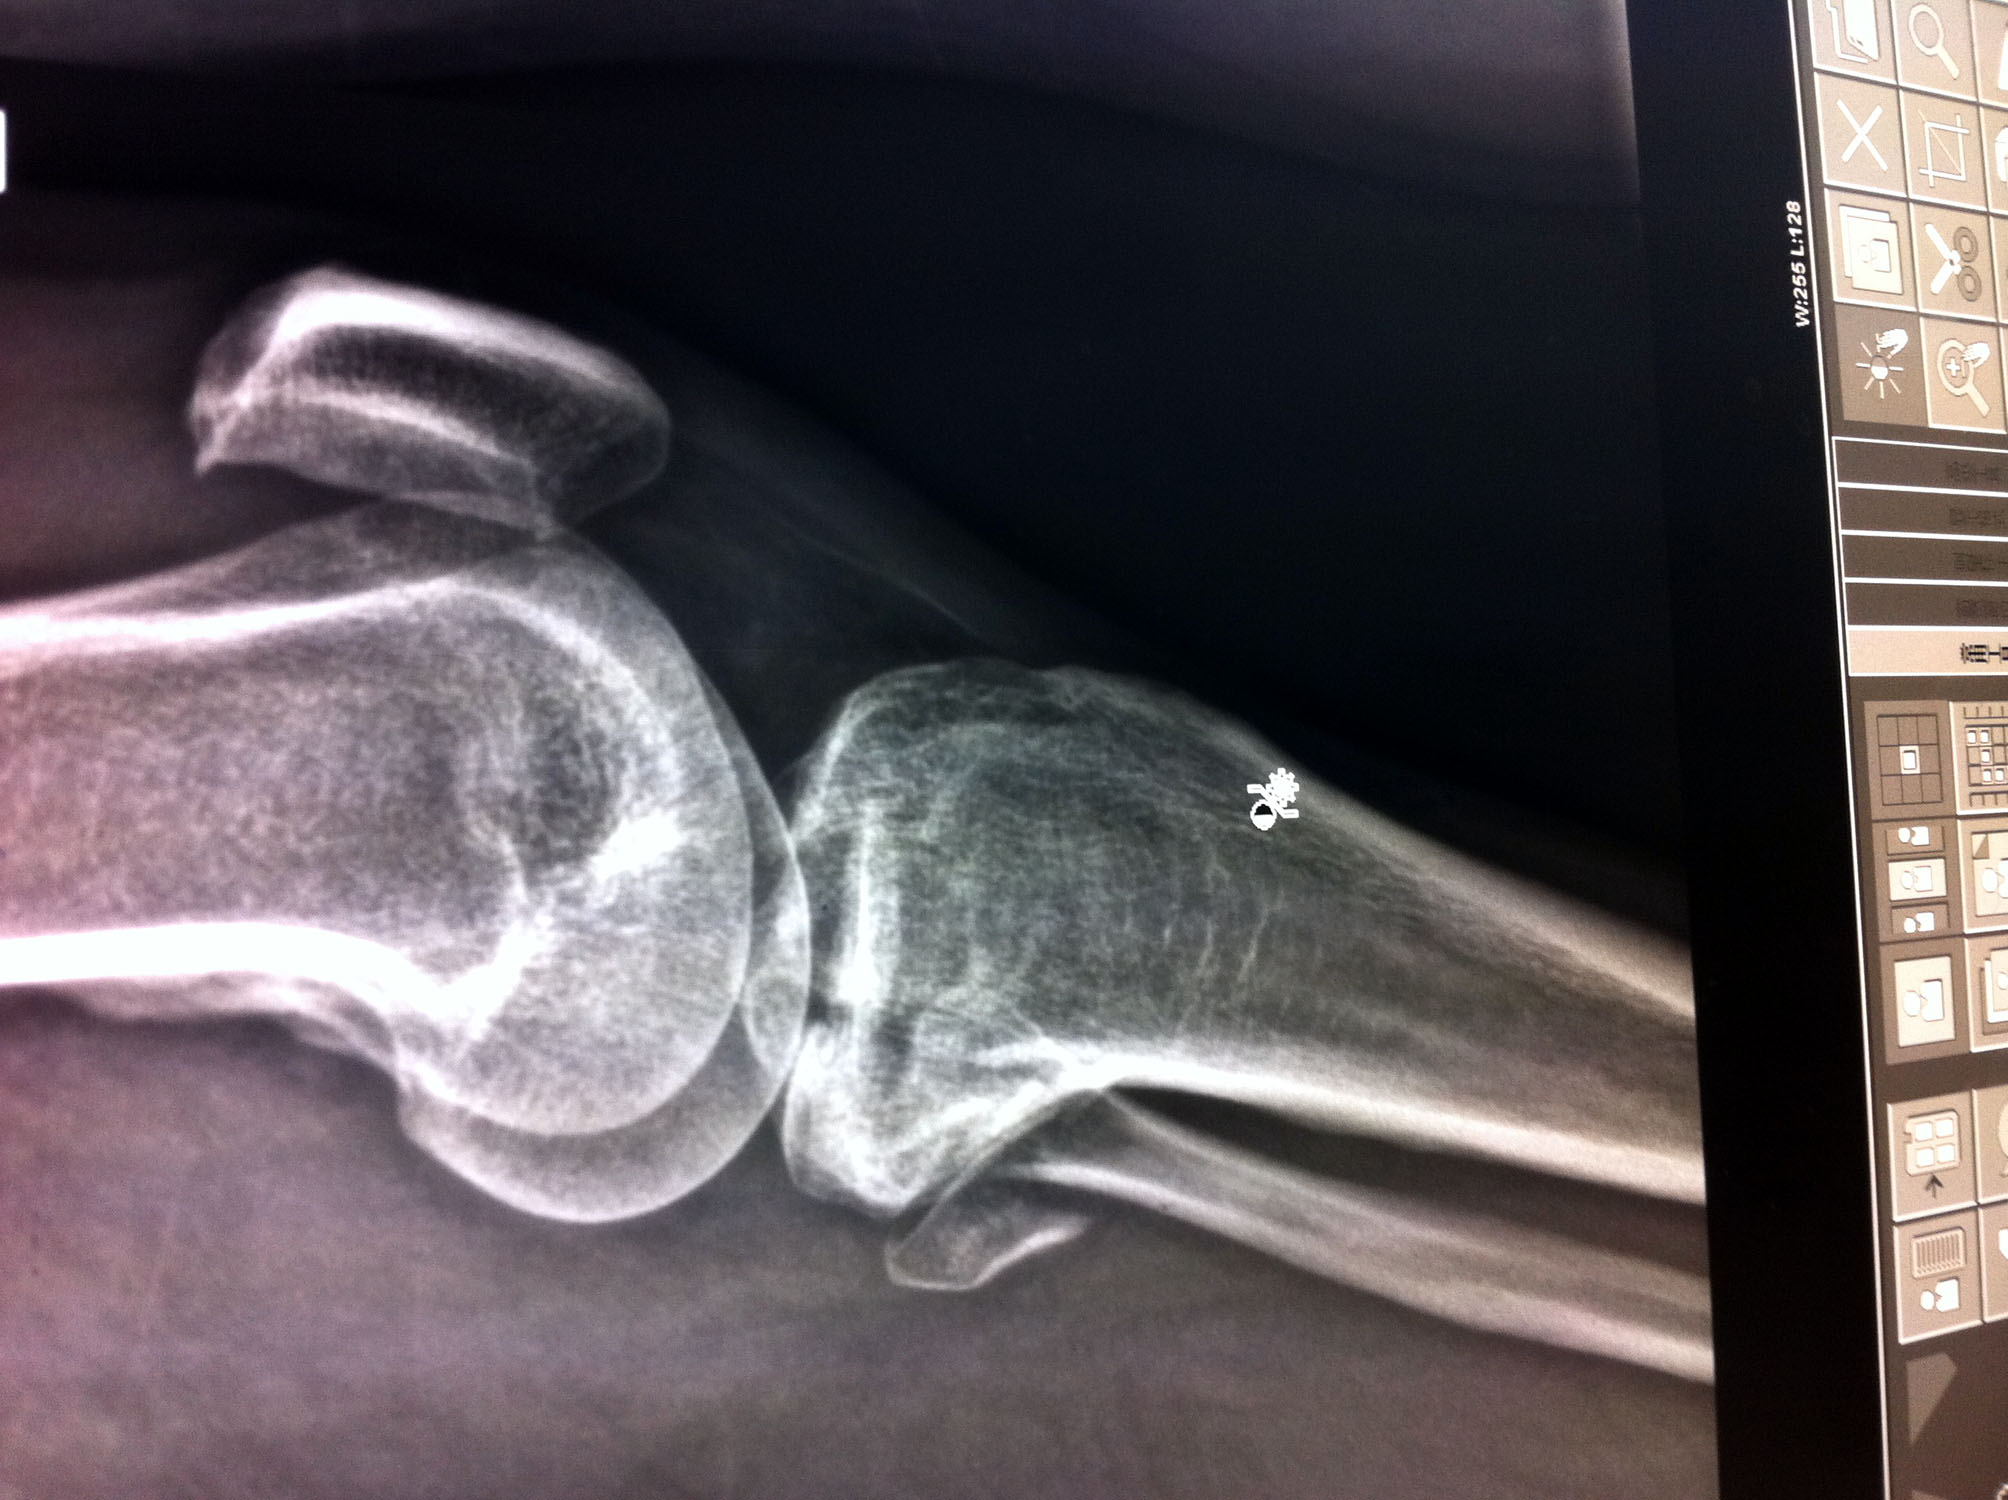

【明慧网二零一四年十一月二十一日】(明慧网通讯员山东报道)二零一四年十月二十五日下午三点,青岛市610(专门迫害法轮功的非法组织)、李沧区610、李沧公安分局和李村派出所警察,绑架、抢劫法轮功学员牛西雹、张定钢、王德铜、李洪升。其中,牛西雹(男、五十二岁)被非法关押在普东看守所至今,张定钢左腿被打骨折。

张定钢左腿被打骨折

张定钢,男、四十八岁,十月二十五日下午被绑架期间,左腿被打骨折,不能行走,用于做生意的面包车,两部手机,家中钥匙、现金约一万六千元,被非法劫走,扣留在李村派出所,家人一直在索要,恶警始终不给,分管的警察的电话:0532-6657661

张定钢于十月二十七日晚被取保回家,一直躺在床上不能下地,家中失去了经济来源,钱物被非法扣留,致使他不能得到及时治疗,家中上有九十岁的老人,下有上学的孩子,妻子还得照顾他,给生活造成困难。